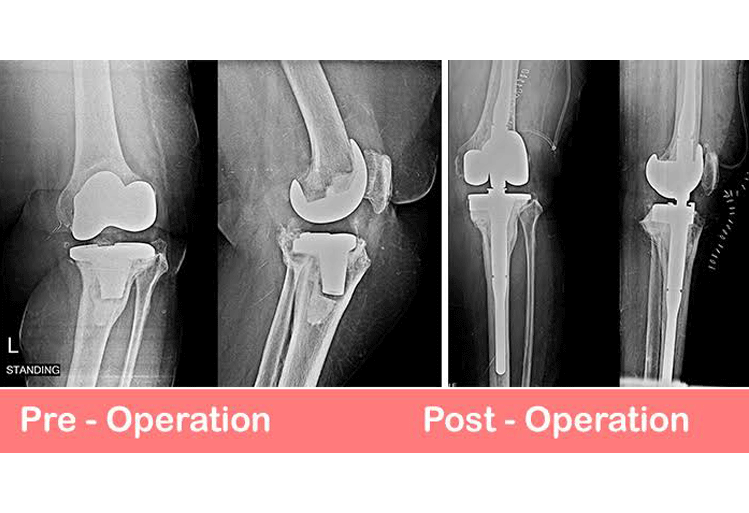

Revision Knee & Hip Replacement

Total Knee Joint Replacement (TKR) revision surgery is an orthopaedic surgical procedure in which the prosthetic pieces(s) of the previous TKR surgery are removed. New prosthetic pieces are then replaced within the knee joint. The components consist of the femoral condyle component, the tibial plateau component, the polyethylene spacer and the patella component. All or some of these may be replaced depending on the reason for replacement.

Revisional TKR surgery is a more complicated operation requiring longer time in theater and rehabilitation is slower and takes a more cautious approach.